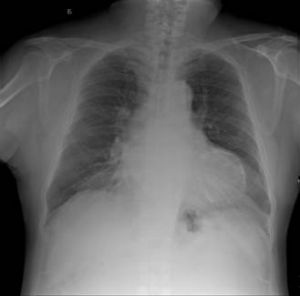

厭氧菌性肺炎X線圖診斷檢查

厭氧菌性肺炎表現2.壞死性肺炎主要表現為在緻密肺段實變陰影中迅速形成空洞,直徑<2cm病變不只侵犯一葉肺。

3.急性肺膿腫表現在大片濃密的陰影中出現圓形透光區,空洞呈圓形,內壁光滑,其內見液氣平面。治療得當,實變陰影與空洞逐漸縮小、消失或殘留索條影。

4.慢性肺膿腫X 線差異較大,膿腔壁較厚,內壁不規則,空洞大小形態不一,可伴有液平面,周邊有纖維索條影,並有不同程度的肺葉收縮。治癒好轉者,有半數繼發支氣管擴張。

5.血行播散所致者,為在一肺或兩肺邊緣部多發的散在小片狀炎性陰影或邊緣較整齊的球形病灶,其中可見膿腔及液平面。

6.膿胸的表現依積膿量的多少而有所差異。患側胸部出現大片濃密陰影,若伴有膿氣胸可見液平面。